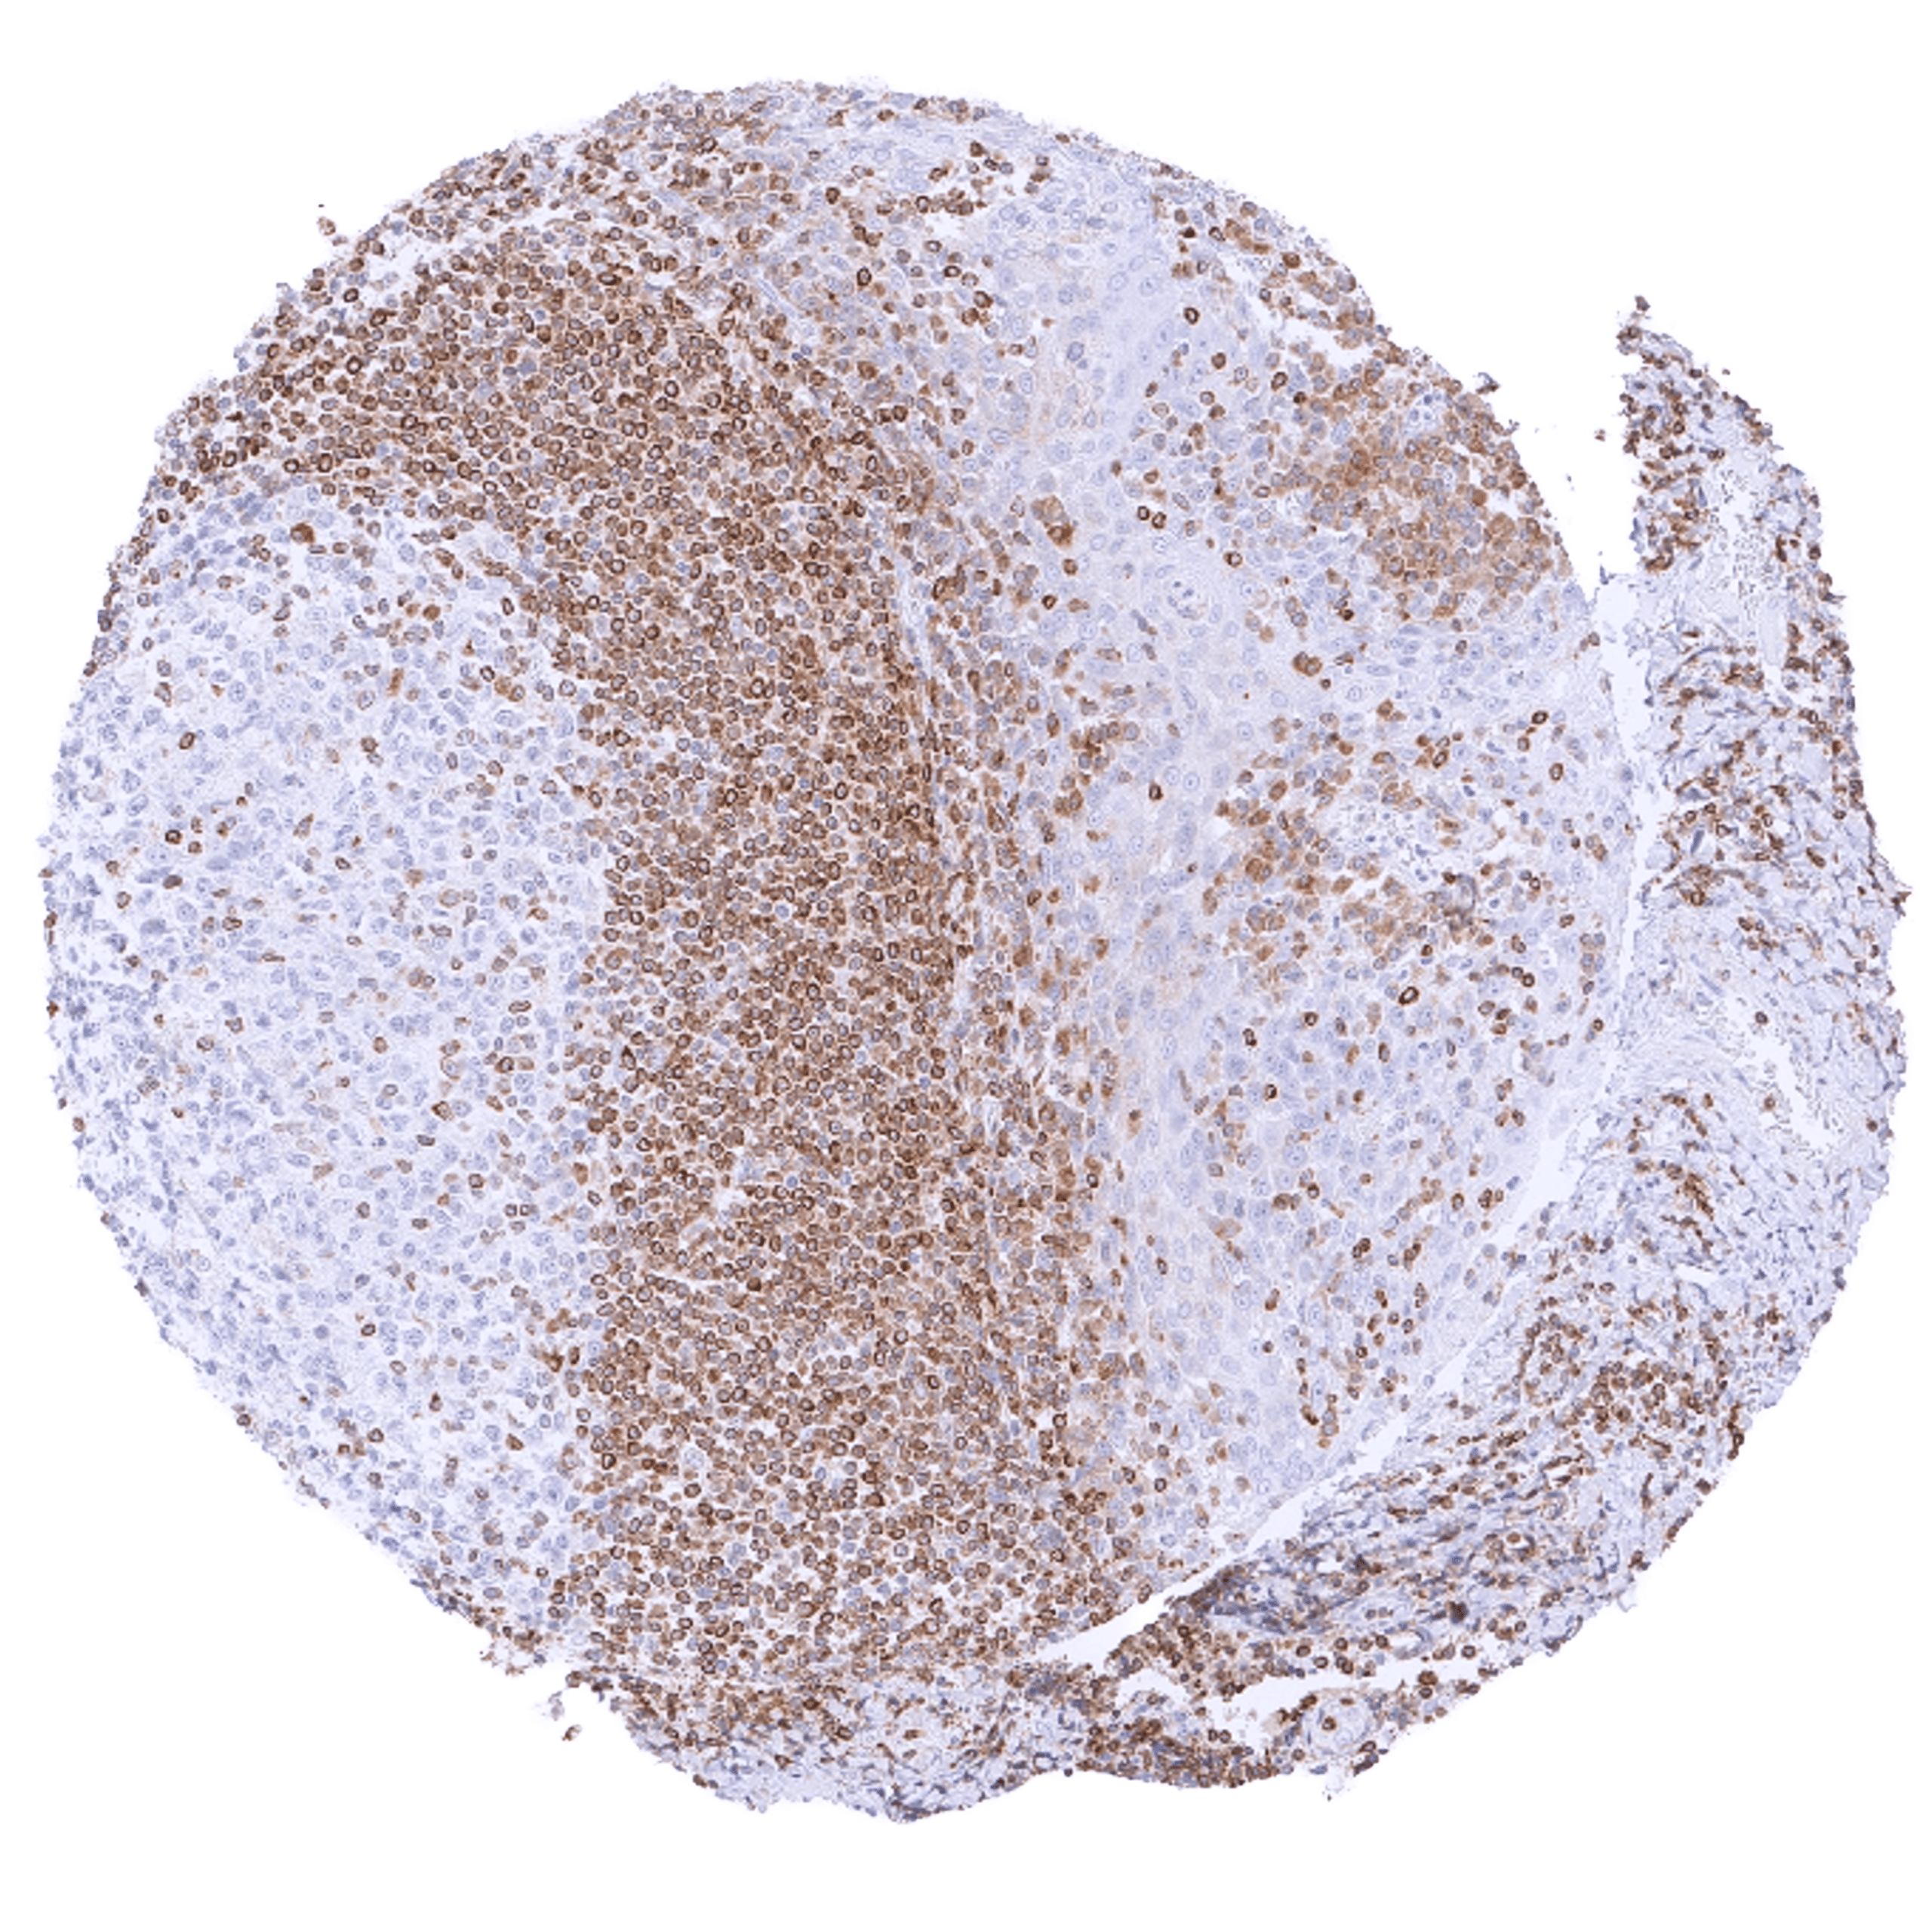

Positive control = Tonsil: A strong cytoplasmic bcl-2 staining should be seen in most interfollicular lymphocytes while most germinal centre cells are bcl-2 negative.

Negative control = Tonsil: The vast majority of lymphocytic cells from germinal centres must be bcl-2 negative while interfollicular lymphocytes are mostly positive.

| Lymph node | Strong bcl-2 positivity of a large fraction of lymphocytic cells in the interfollicular area and around germinal centres while almost all cells in germinal centres are bcl-2 negative. | |

| Tonsil | Strong bcl-2 positivity of a large fraction of lymphocytic cells in the interfollicular area and around germinal centres while almost all cells in germinal centres are bcl-2 negative. Squamous epithelium is bcl-2 negative although the basal cell layer may show weak positivity. | |